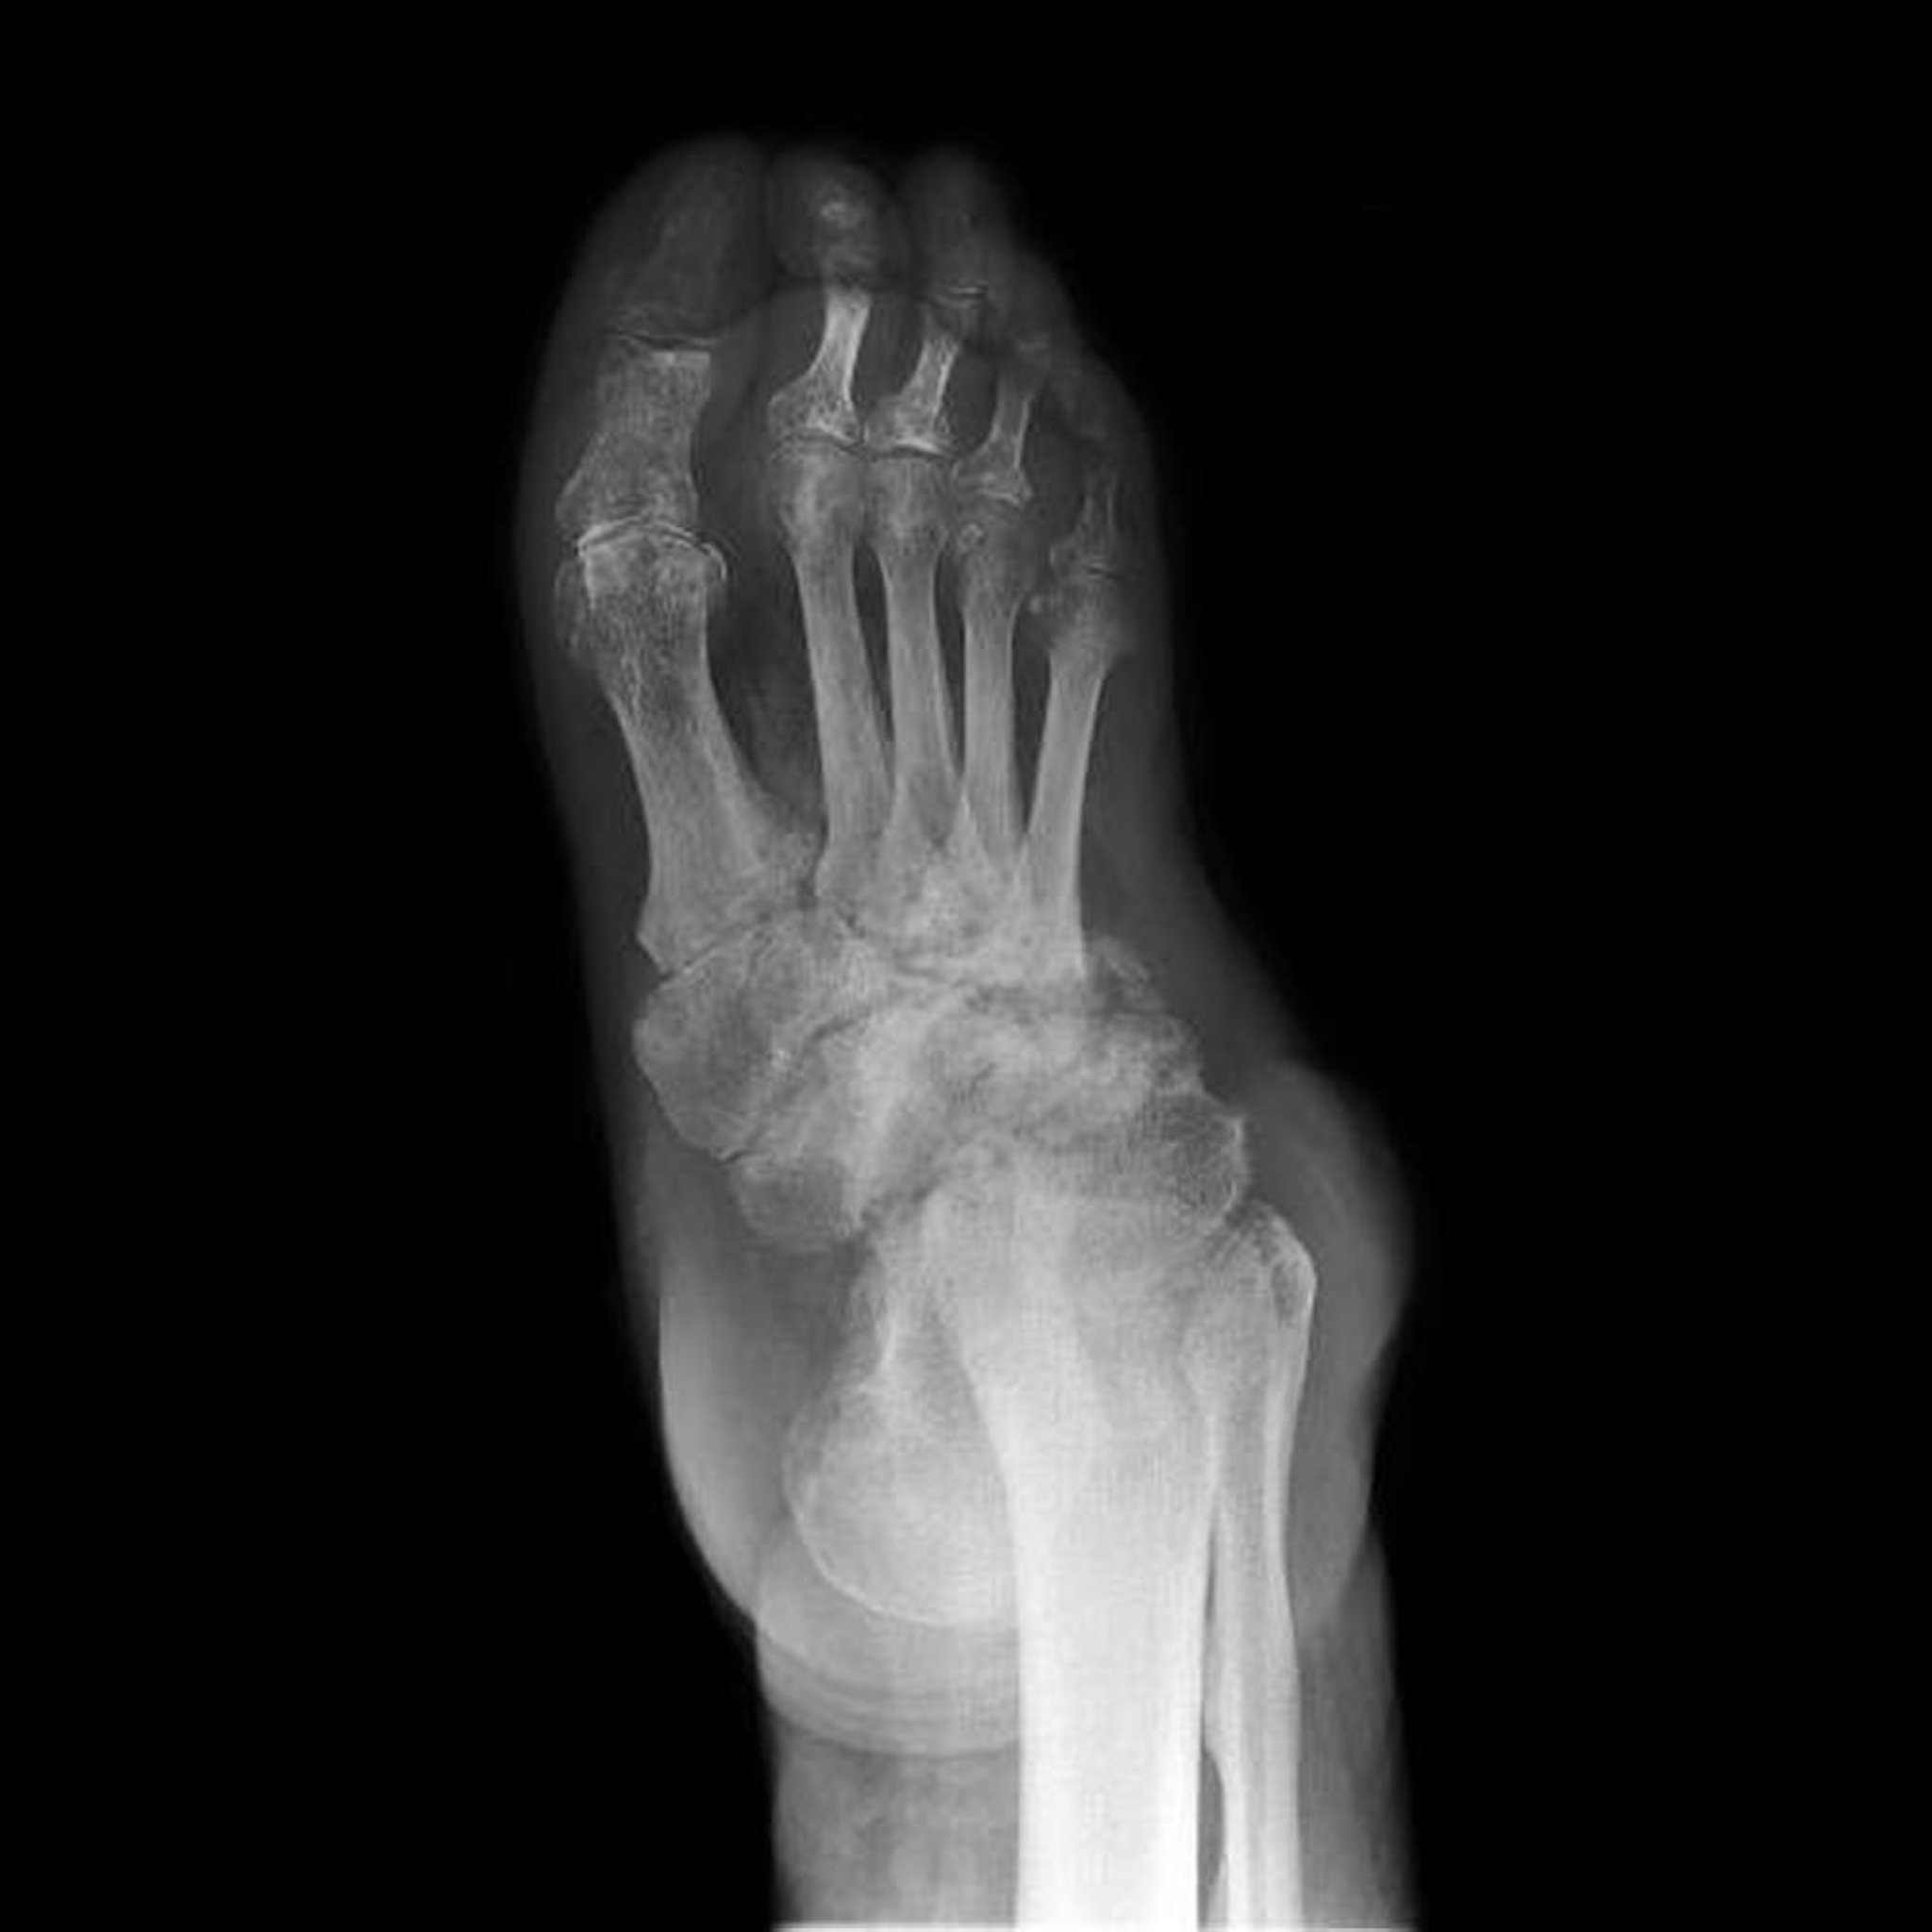

足の神経病性関節症

このX線写真には,足の神経病性関節症(別名シャルコー足)が認められる。足根骨の破壊,変形,および関節裂隙狭小化が広範囲にみられる。